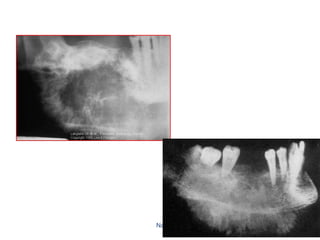

Central Osteoma anterior to remaining roots of lower 7

Peripheral osteoma in right angle of the mandible

It may confused with calcified lymph noads